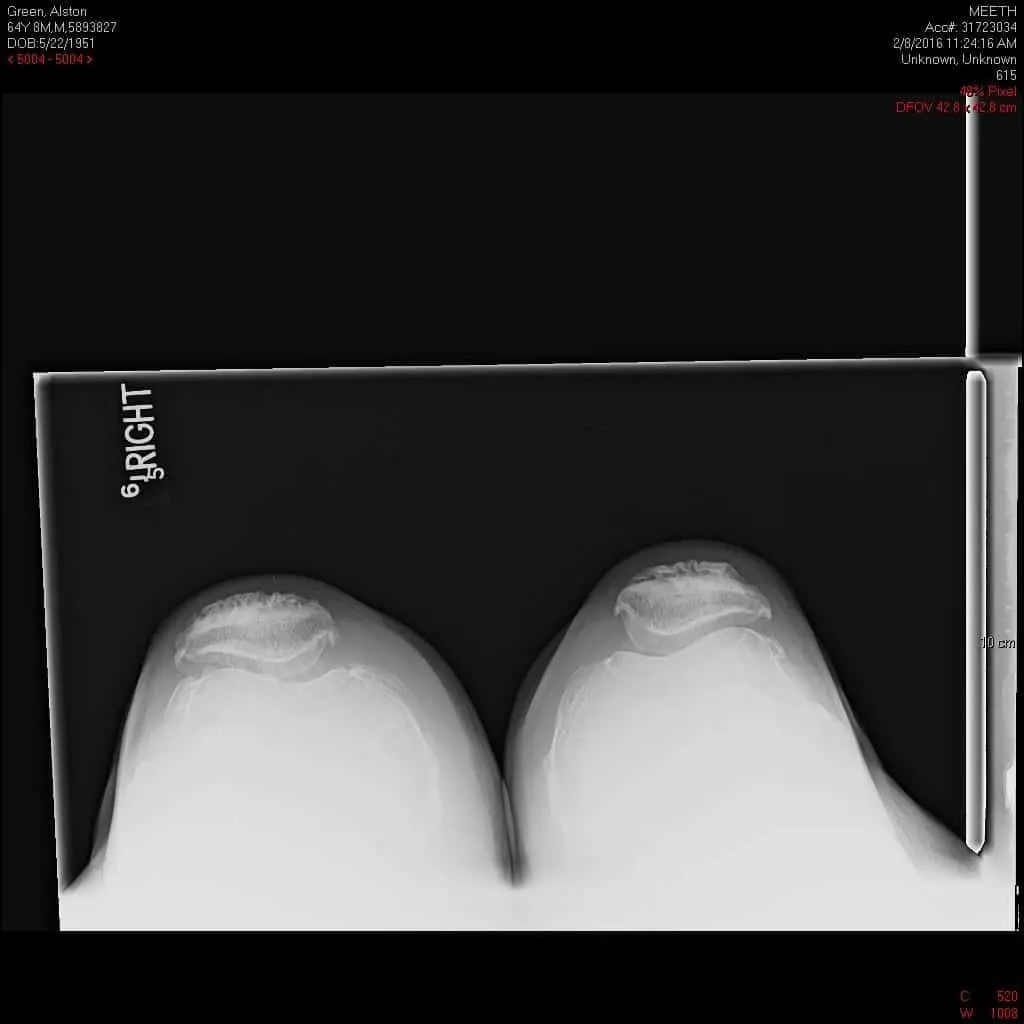

Imaging studies revealed severe tricompartmental osteoarthritis of the right knee. Considering the lifestyle limiting knee pain, the patient was advised right total knee replacement. All the risks, benefits and alternatives were discussed in detail with the patient. The patient agreed to go ahead with the procedure.

Preoperative X-ray of the right knee in lateral view and skyline view.